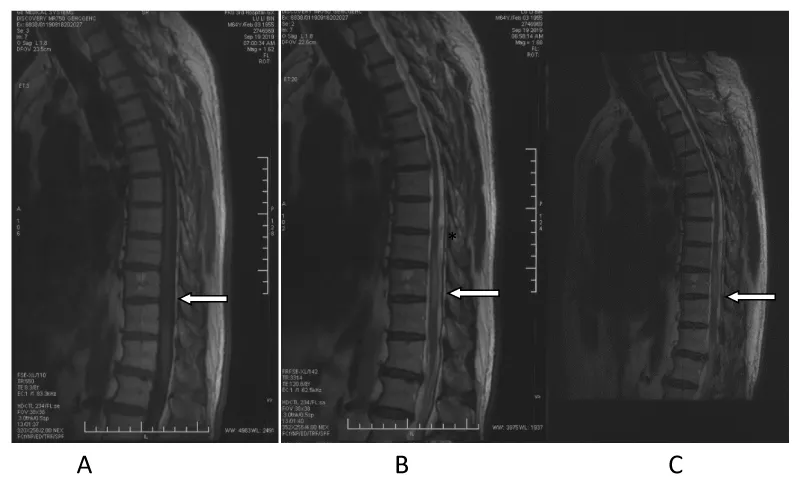

In March 2019, the 62-year-old male patient appeared numbness and weakness of the foot to knee joint, unstable walking, dysuria and constipation. It worsened gradually in several months. MRI of thoracic vertebrae was performed (Figure 1) and DSA showed normal. He was treated for benign prostatic hyperplasia, lumbar disc herniation, and demyelination of the nervous system, but none of the treatments worked. After admission, Cerebrospinal Fluid (CSF) examination showed slightly elevated biochemical protein of 0.73g/L. No abnormality was found in thyroid antibody, ANA, ENA spectrum and ANCA. Negative antibody against measles virus. PPD test was negative, and no abnormality was found in tb-spot test. CSF cytology showed no tumor cells. We considered a possible vascular malformation of the spinal cord, and the result of DSA confirmed it (Figure 2). Then, the dural arteriovenous fistulectomy was performed through the posterior median approach under general anesthesia (Figure 3). After 6 weeks of follow-up, numbness and weakness were reported to be better than before, and he could walk independently.